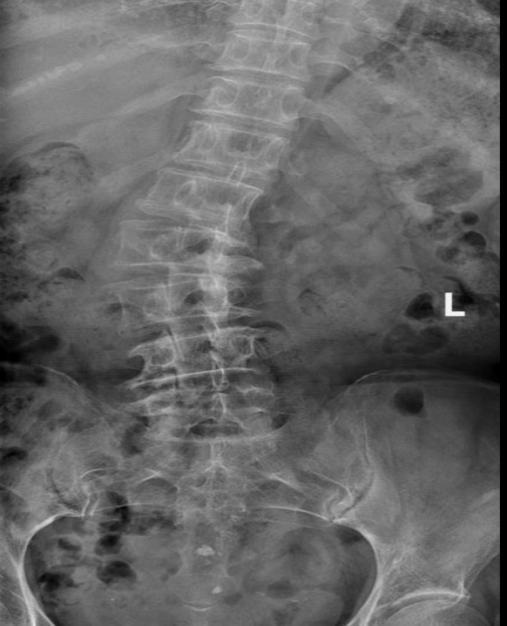

患者郝女士因腰椎退变性侧弯畸形无法久站、不能长距离行走,大腿疼痛,严重影响正常生活。脊柱侧弯矫形术因涉及脊髓神经安全,风险极高,属脊柱外科难度“天花板”级手术。患者经多地就诊后,因惧怕手术风险未接受治疗,经过多方对比最终选择到四师总医院就诊。

四师总医院脊柱外科团队在充分评估患者病情及风险后,决定在脊柱内镜辅助下进行脊柱侧弯矫形手术。手术利用内镜微创优势,完成多个间隙的微创减压,既减少创伤,又避免额外输血。术后患者恢复良好,疼痛缓解,已能正常站立行走,生活质量显著提升。